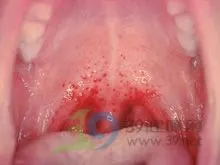

后来看过发现口腔上颚舌根上方有破损.请问下可能是什么病.

口腔上颚红点不疼不痒.最近嗓子痰多.不舒服

两天后,晨起孩子叫喉咙痛,舌苔偏黄,拍下口腔内上颌局部红伴血点的

腭部可见小出血点

也就是说口腔疱疹是一个变化过程,早期是红点,然后发展为小水泡,最后